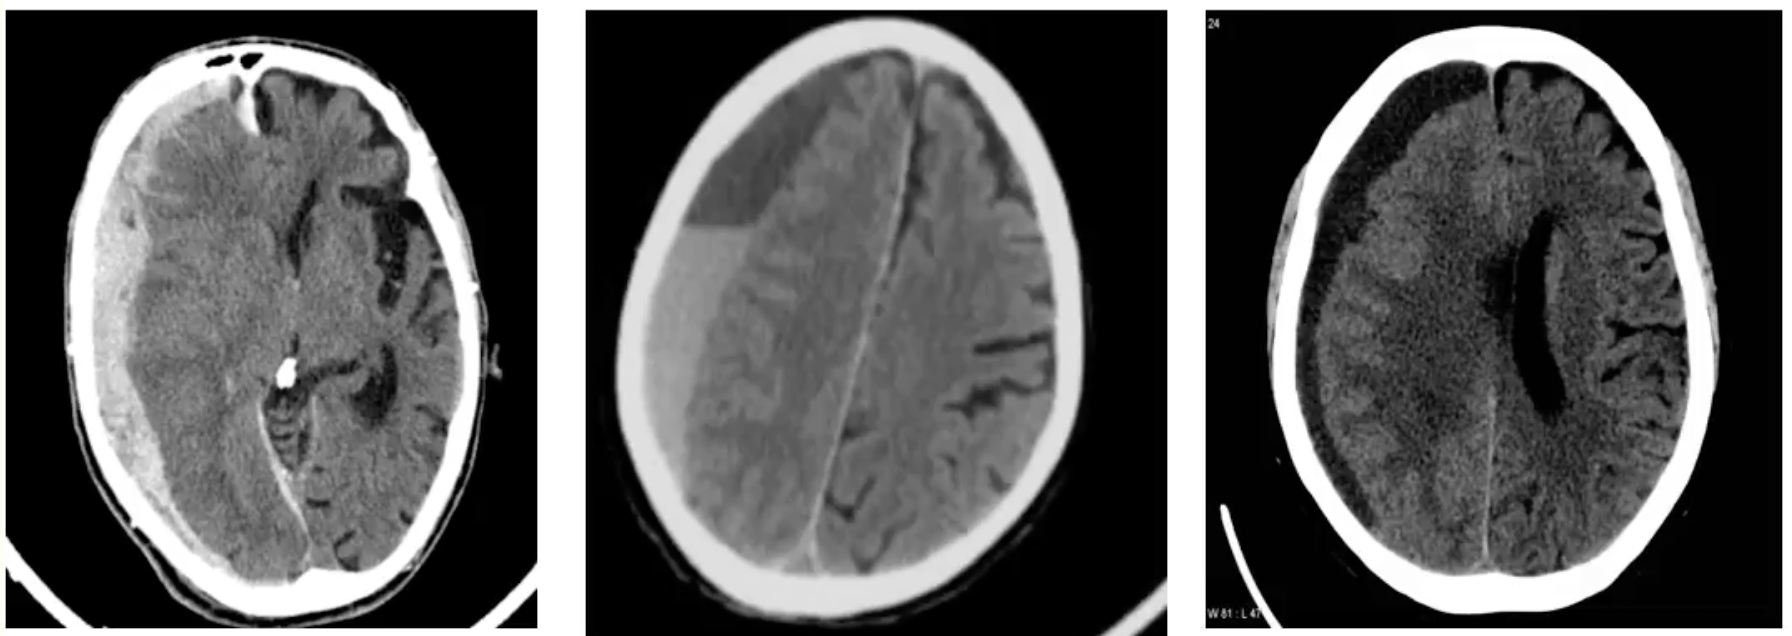

Classificação hematomas subdurais

agudos: < 3 dias → hipertenso em TC

subagudos: 3 dias - 3 semanas → isodenso (= tecido cerebral)

crónicos: >3 semanas → hipodenso